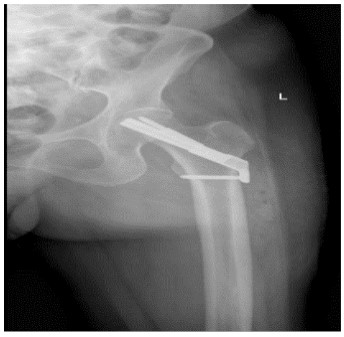

A female, aged 55, with 153 cm in height, 85 kg in weight and 36.3 in BMI. She was admitted to hospital on July 24, 2021 due to severe osteoarthritis of the right knee. Physical examination manifested severe varus deformity of affected limb with limited flexion and extension activities, with ROM: 80°-10°-0° (Figure 1). The patient received TKR on July 27, 2021. She was permitted walking one day post-operatively, and was discharged one week later (Figure 2).

Figure 1: Case 1

Case 2 was also a female with 58 in age, 160 cm in height, 65 kg in weight and 25.4 in BMI. She was admitted to hospital on December 08, 2020 due to severe osteoarthritis of the left knee. Physical examination manifested severe deformity of the affect limb with limited flexion and extension activities, with ROM: 100°-10°-0° (Figure 5).

Figure 5: Case 2 prior to admission

As for the reasons, we deduced that post-operative changes in biomechanical axis of knee joint, increasing activity levels, osteoporosis and BMI mass index played great role in leading to stress fracture of femoral neck. Furthermore, the bilateral varus deformity of the knee joint was severe in these two patients, lower limb load axis after TKR is significant changed (Figures 1,2,5,6), resulting in concentrated creation on the femoral neck cortex. When full weight bearing, activity levels increased and excessive loading of the hip may cause the tendency of hip varus, bring about the possibility of fracture. Those two patients (Tables 1,2), Osteoporosis index 25 hydroxyvitamin D was lower than normal, they are osteoporosis, Bone density and mass decrease, and bone microstructure is destroyed, resulting in increased bone fragility, which can lead to fractures. The BMI of case 1 is 36.3, severe obesity, excessive loading of the right hip, so we assume that changes in biomechanical axis of knee joint after TKR, activity levels increased, osteoporosis and BMI mass index can lead this infrequent complication.